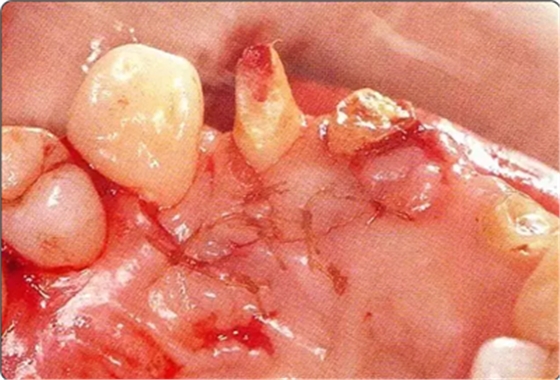

圖10-3 考慮到審美性,應(yīng)用牙齦乳頭保存術(shù)(Papilla preservation technique),進(jìn)行了自體骨移植。

圖10-4 骨缺損部位進(jìn)行骨修整結(jié)束的狀態(tài)。